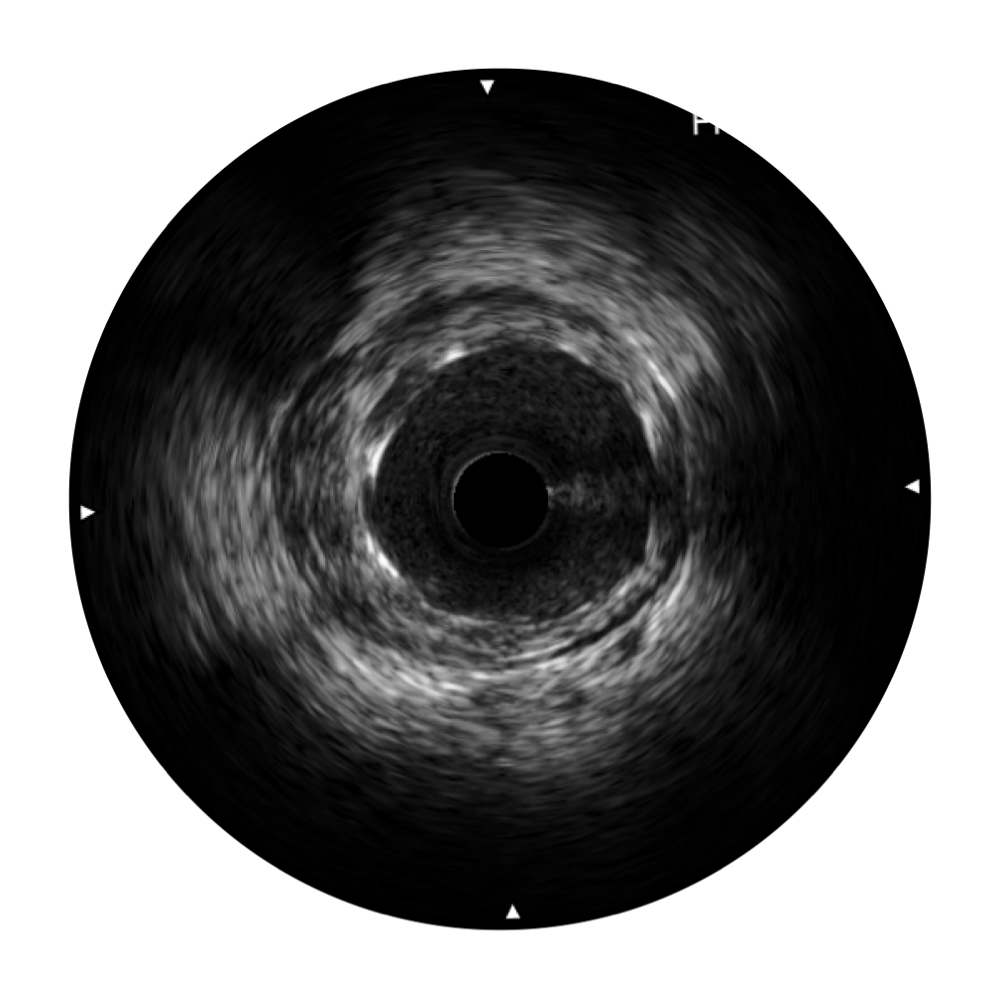

• 传统IVUS图像

对比传统IVUS导管成像,16877太阳集团宽频IVUS图像的近场支架梁显影更细腻,远场中膜外血管仍清晰可辨,兼顾远中近,兼顾分辨力与穿透深度